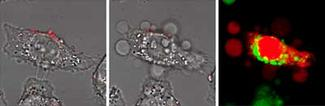

Having developed a method of tracking nanorods, the team then looked at ways to locate them near to tumor cells. The membranes of tumor cells contain an unusually large number of receptor sites for folic acid, a form of vitamin B that many tumor cells crave. So the team attached folic acid to the nanorods. That helped to steer the nanoparticles to tumor membranes in cell cultures.

The two-photon process with the laser in pulsed mode was used to identify the positions of nanorods attached to the membranes of the tumor cells. Then the researchers switched the laser to continuous mode. In that state, the laser generates higher average power and heats the nanorods. As they heat up, the nanorods ionize the molecules around them. “This generates a plasma bubble that lasts for about a microsecond in a process of cavitation,” Wei explains. “Every cavitation is like a tiny bomb. Then, suddenly, you have a gaping hole where the nanorod was.”

In their initial experiments, the researchers waited for the nanorods to penetrate into the cells before heating them. They soon found, however, that they could kills the cells just as effectively, and at the expense of far less power, by exposing them to the continuous laser light while they were still on the membranes’ surfaces. “If you wait until the nanorods are inside the cells, you really have to pump up the laser power,” Cheng says. “So localizing the nanorods on the cell membrane strongly influences their ability to inflict cell damage.”